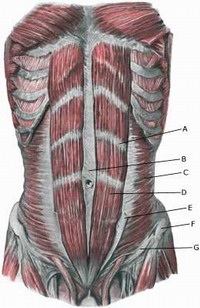

linea alba (B):

linea alba (B):

linea alba (B):